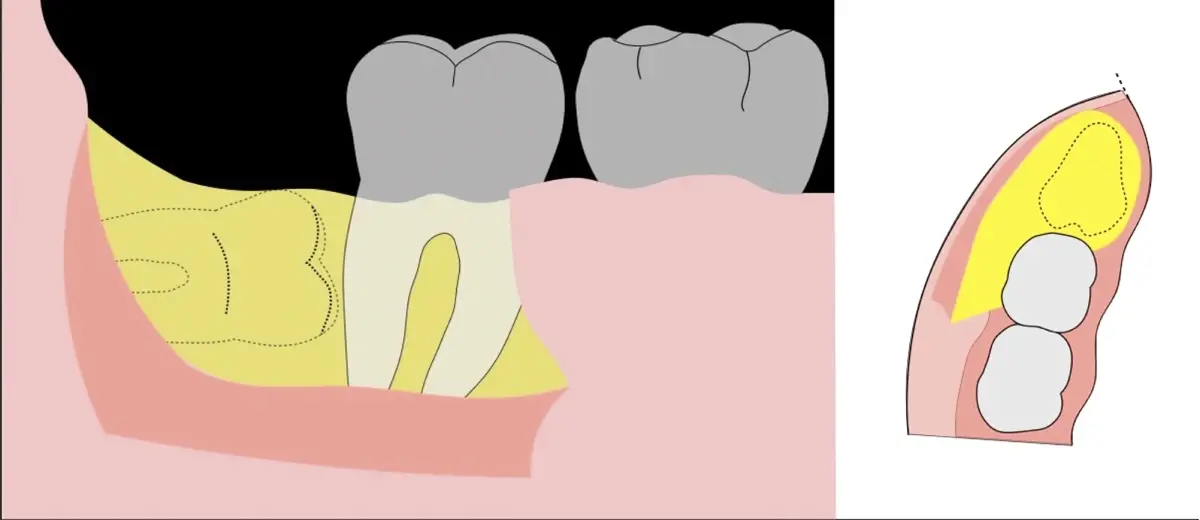

El procedimiento puede variar en su complejidad dependiendo de su ubicación, profundidad, angulación, y la densidad ósea circundante.2 Uno de los pasos más críticos y cruciales en la extracción es la osteotomía previa y concomitante al acceso quirúrgico del diente, para lo cual se utilizan diversos instrumentos como cinceles y martillos, instrumental rotatorio o de corte por ultrasonido.3

Para realizar la técnica de extracción de una tercera molar, una vez que se ha confirmado su diagnóstico, se debe considerar la posición del diente (vertical, mesioangular, distoangular, horizontal u otras), profundidad y grado de impacto, obstrucción a la erupción asociada a la segunda molar, morfología de la raíz (la curvatura de las raíces controla el camino de la exodoncia), relación con el canal del conducto dentario inferior, la patología asociada, la densidad ósea y la Integridad de la segunda molar.